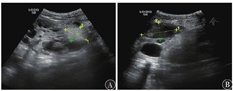

患者男,19岁,因"无诱因右侧背部及中上腹疼痛"入院。既往体健,无肝炎、结核及其他传染病史。无多囊肾家族史。尿常规检查:潜血3+,蛋白+;尿点式蛋白检查:尿蛋白定性+,点式总蛋白0.71 g/g,点式白蛋白57.13 mg/mmol,尿白蛋白182.80 mg/L,尿总蛋白0.26 g/L。肾功能检查:血肌酐169.00 μmol/L,血尿酸446.00 μmol/L,降钙素原0.564 pg/L。胰腺炎指标未见异常。多普勒彩色超声检查:双侧多囊肾,多发错构瘤。双肾体积明显增大,左肾165 mm×104 mm×83 mm,右肾206 mm×131 mm×99 mm,均可见多个大小不等实性高回声,左侧较大者约41 mm×32 mm,右侧较大者75 mm×36 mm。双肾内弥漫分布多个大小不等的囊性回声,左侧较大者约39 mm×23 mm,右侧较大者52 mm×36 mm。囊腔互不连通,壁薄,内透声差,后方回声增强,囊外肾实质回声菲薄,右肾中上部周边见约113 mm×102 mm不均质回声包块,疑是血肿。见图1。诊断:多囊肾破裂出血;临床排除糖尿病肾病、狼疮肾病和高血压肾损害。

注:A:左侧肾囊肿;B:右侧肾囊肿